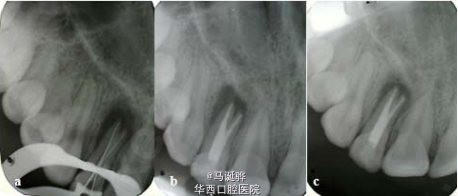

越来越逆天的侧切牙

伴随着越来越多的侧切牙双根管被大家发掘,大家对这个小牙齿是不是有点胸有成竹。但是,道高一尺魔高一丈,侧切牙也越来越不让人省心了。